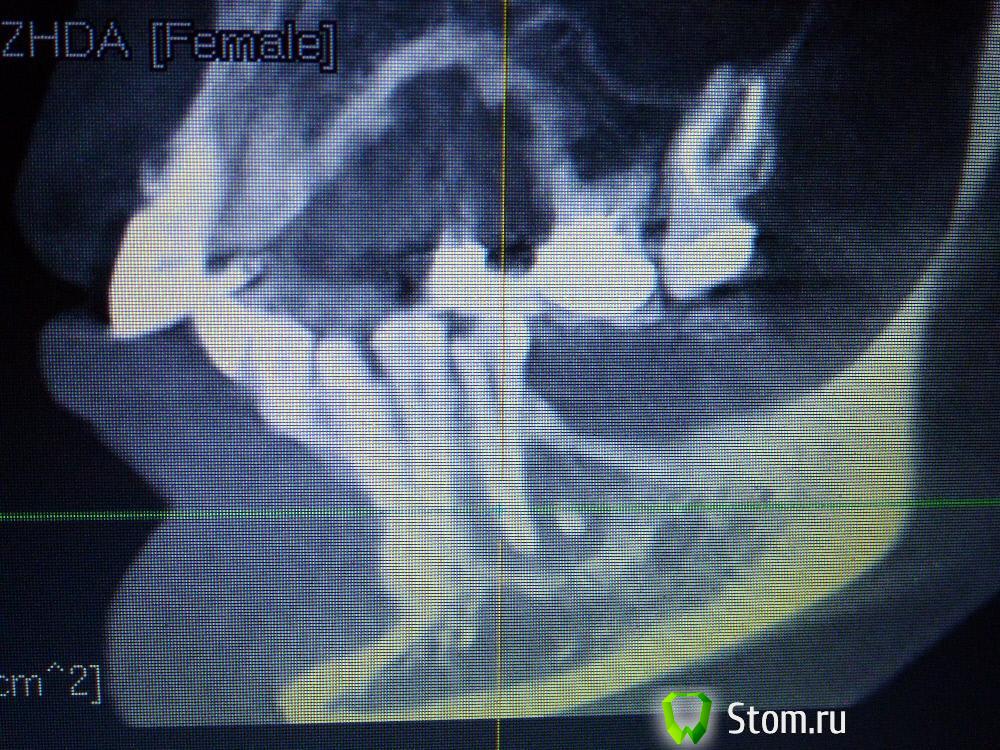

IvanK Опубликовано 25 ноября, 2011 Поделиться Опубликовано 25 ноября, 2011 Коллеги , посоветуйте Ваш план лечения.Пациентка обратилась с целью протезирования. Была направлена на ОПТГ. Обнаружены "кисты".Предположены амелобластома или первичная киста. Направлена на кафедру в 1 мед. Сказали, что "обычные кисты".Вижу 2 варианта:1). эндодонтическое лечение, цистэктомия, гистология, резекция верхушек корней, наблюдение, далее костная пластика?, имплантация. 2) Удаление зубов с периапикальными изменениями + 8-ка, гистология, пластика, имплантация боковых отделов. Ссылка на комментарий

Corvalus Опубликовано 26 ноября, 2011 Поделиться Опубликовано 26 ноября, 2011 Эндодонтическое лечение: 45,44,33-го тоже он в зоне кисты,34,36. Хуже дела обстоят с 35-м, глянуть бы прицельный снимок, если периапикальные изменения есть, то шуруп трудно достать будет. Обязательно реэндодонтия 43. Далее цистэктомия без всяких резекций с обязательной гистологией. Заполнять кисты не стал бы, достаточно крови, очаг гнойный. Через несколько недель парадонтологическое лечение, после костная пластика с отсроченной имплантацией. И в конце рациональное протезирование одиночными коронками. При нормальном эндодонтическом лечении рецедива кист не должно быть, а если и будет, то не на всех зубах сразу. Себе зубы удалять не стал бы, опыт лечения таких зубов есть, с имплантацией всегда решить можно по ходу поступления проблем. Второй вариант имеет место быть. Объяснить пациентке все за и против, пусть сама выбирает. Ссылка на комментарий